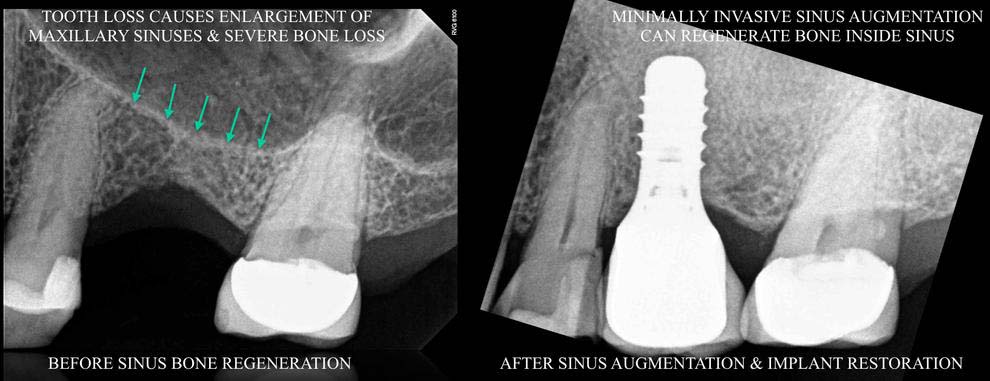

- MINIMALLY INVASIVE SINUS AUGMENTATION